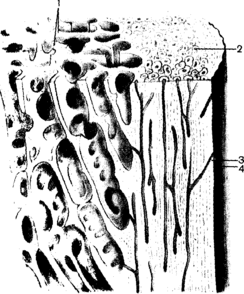

Наружный слой кости представлен толстой (в диафизах трубчатых костей) или тонкой (в эпифизах трубчатых костей, в губчатых и плоских костях) пластинкой компактного вещества, substantia compacta. Под компактным веществом располагается губчатое (трабекулярное) вещество, substantia spongiosa (trabe-cularis), пористое, построенное из костных балок с ячейками между ними, по виду напоминающее губку. Рисунок строения кости хорошо виден на срезах (шлифах) костей. Внутри диафиза трубчатых костей находится костномозговая полость, cavitas medullaris, содержащая костный мозг. Компактное вещество построено из пластинчатой костной ткани и пронизано системой тонких питательных канальцев, одни из которых ориентированы параллельно поверхности кости, а в трубчатых костях - вдоль длинного их размера (центральный, или гаверсов, канал), другие, прободающие (каналы Фолькмана) – перпендикулярно поверхности. Эти костные канальцы служат продолжением более крупных питательных каналов, candles nutrlcii (nutriensii), открывающихся на поверхности кости в виде отверстий, один - два из которых бывают довольно крупными. Через питательные отверстия в кость, в систему ее костных канальцев проникают артерия, нерв и выходит вена.

Стенками центральных каналов служат концентрически расположенные костные пластинки в виде тонких трубочек, вставленных одна в другую. Центральный канал с системой концентрических пластинок является структурной единицей кости получил название остеона, или гаверсовой системы. Пространства между остеонами выполнены вставочными промежуточными, интерстициальными) пластинками. Наружный слой компактного вещества кости образован наружными окружающими пластинками. Внутренний слой кости, ограничивающий костномозговую полость и покрытый эндостом, представлен внутренними окружающими пластинками. Остеоны и вставочные пластинки образуют компактное корковое вещество кости.